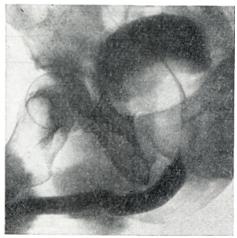

Применяют экскреторную урографию, цистографию и уретроцистографию; наиболее рациональна лакунарная уретроцистограмма по Кнайзе и Шоберу (рис. 4). Кислород, введенный по катетеру в количестве 150—200 мл, растягивает мочевой пузырь в виде купола. Введенное вслед за кислородом жидкое контрастное вещество (20% раствор сергозина в количестве 20 мл) располагается в области дна мочевого пузыря, выявляя внутрипузырный рост аденомы предстательной железы. Этим методом определяют ряд типичных рентгенологических симптомов: «берета» (рис. 5), удлинения мочеиспускательного канала (рис. 6), «клинка сабли» (рис. 7), приподнятого дна.

Экскреторная урография, помимо определения функции почек, указывает на состояние нижних отрезков мочеточников, которые крючкообразно приподнимаются кверху, давая изображение «рыболовного крючка» (рис. 8). Рентгенологическое исследование выявляет также сопутствующие заболеванию камни и дивертикулы.